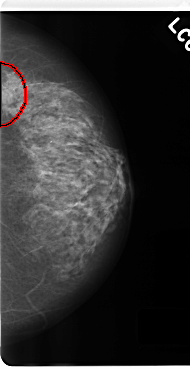

C_0228_1.LEFT_CC

LEFT_CC LINES 4792 PIXELS_PER_LINE 2464 BITS_PER_PIXEL 12 RESOLUTION 50 OVERLAY

FILE: C_0228_1.LEFT_CC.OVERLAY

TOTAL_ABNORMALITIES 1

ABNORMALITY 1

LESION_TYPE MASS SHAPE ROUND MARGINS CIRCUMSCRIBED

ASSESSMENT 4

SUBTLETY 5

PATHOLOGY MALIGNANT

TOTAL_OUTLINES 1

BOUNDARY